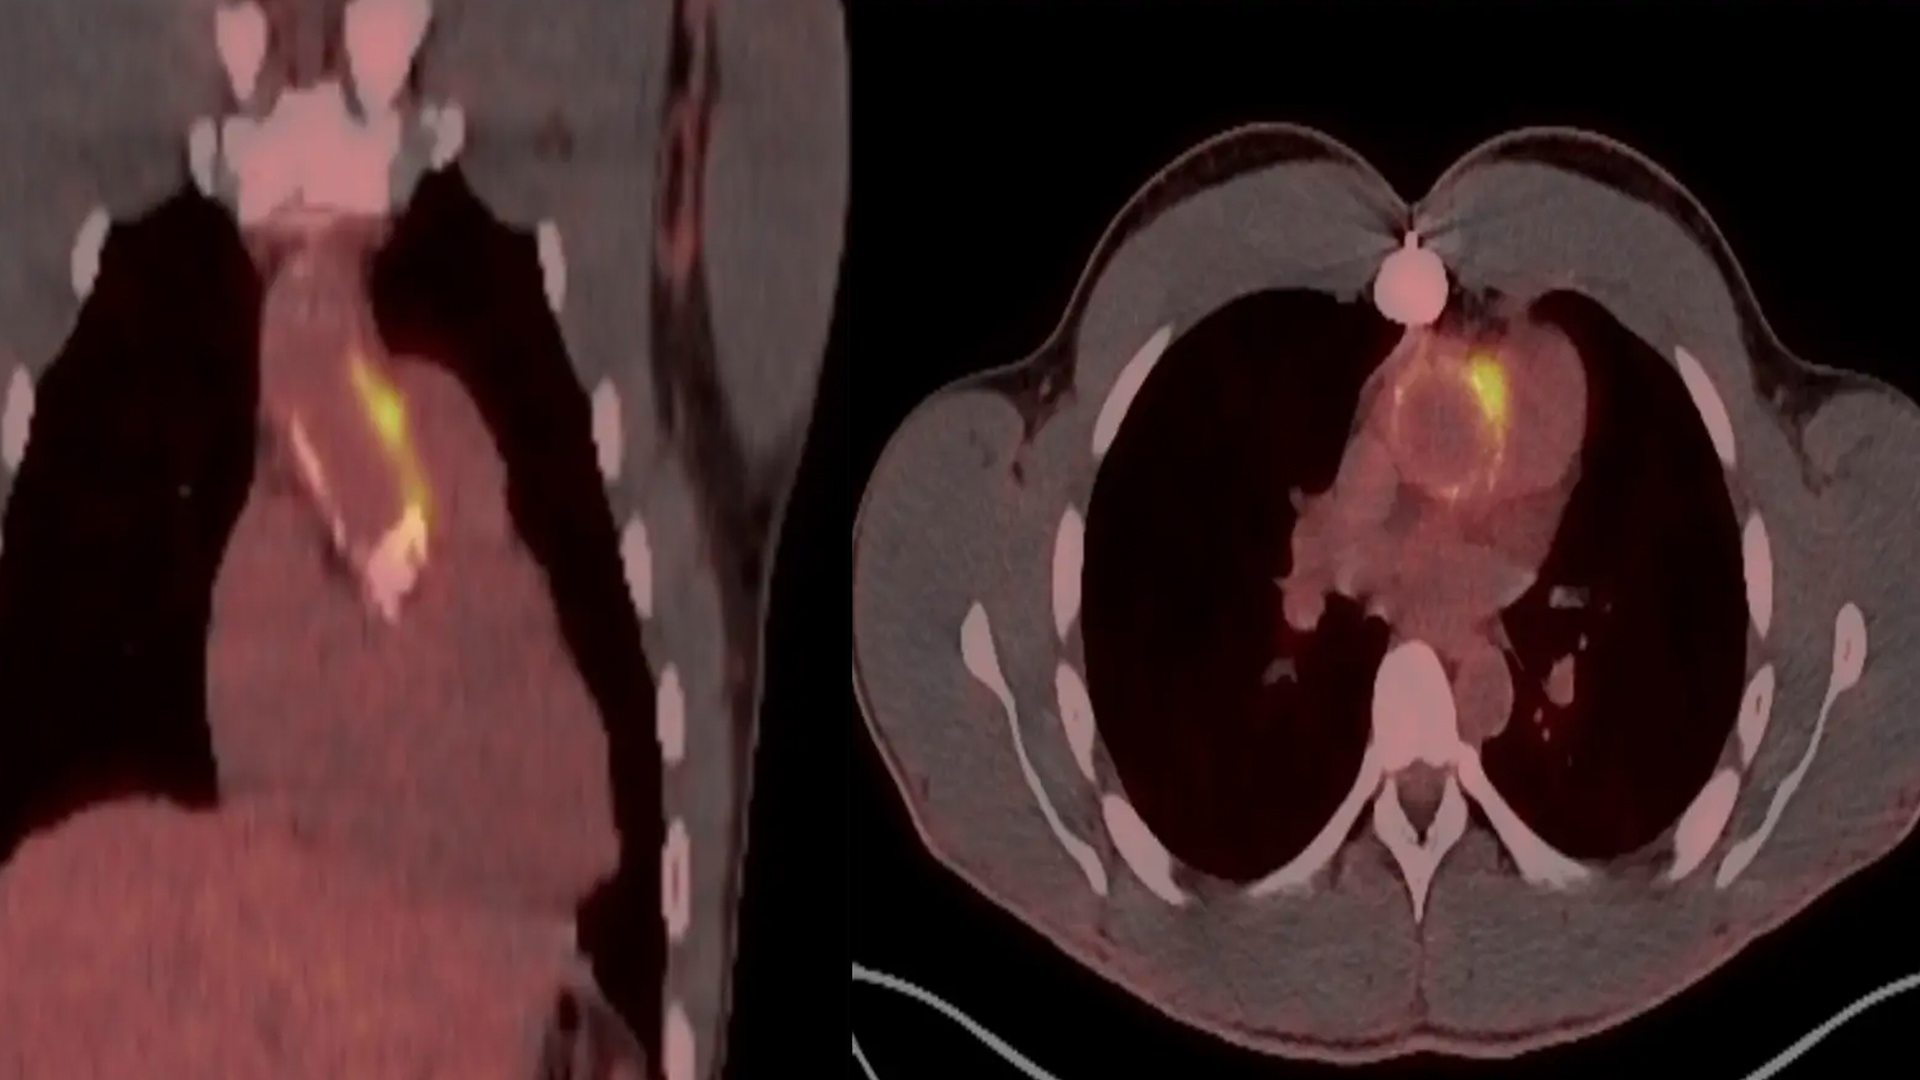

Imaging Highlights

Deliver world-class education in cardiac CT today, and multimodality imaging (MRI, PET, echo) tomorrow.